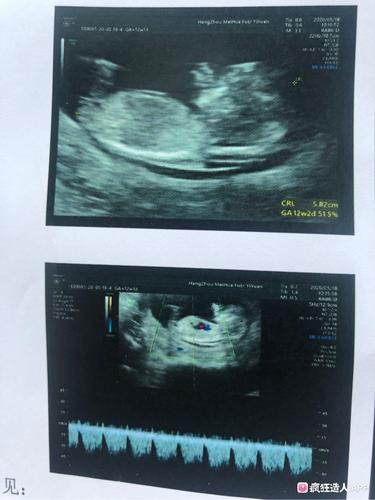

nt女孩图片,12周nt男宝特点 男孩

nt照 猜猜男女

nt看男女 nub图片非常清晰的情况下准确率还是挺高的

nt看男宝女宝

12周nt男宝特点 男孩

男孩的nt图

男孩nt图的特点

nt图男宝图片

12周男宝b超图片

孕12周男宝生殖彩超图

12周胎儿图片

nt女孩图片彩超

NT单子女孩三道杠图片